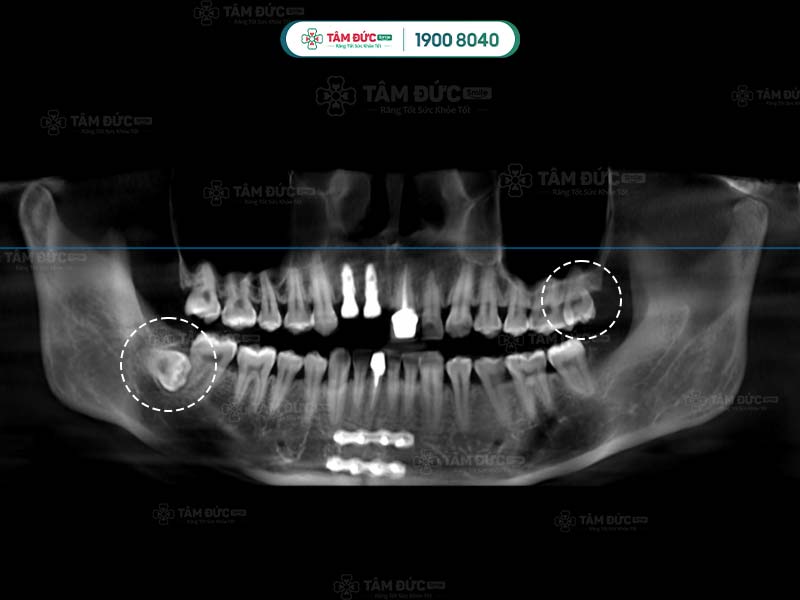

Răng khôn qua phim chụp X-Quang

Hình dạng của chân răng khôn hay còn gọi là gốc răng khôn ở mỗi người có sự khác biệt. Răng khôn có hình dáng khác với những chiếc răng còn lại, chúng hầu như có từ 2, 3 thậm chí là 4 gốc răng. Các chân này thường hợp nhất với nhau tạo thành chân lớn. Tuy nhiên, một số khác lại cuộn tròn hoặc xòe ra các hướng khác nhau.

Một số trường hợp đặc biệt, răng khôn có thể có nhiều hơn 4 chân răng. Chính vì thế, việc biết được răng khôn có mấy chân là điều cần thiết giúp bác sĩ lựa chọn giải pháp nhổ răng khôn an toàn nhất.

Một số ít trường hợp, răng khôn không mọc ở cả 4 vị trí. Có người chỉ mọc 2 chiếc, có người chỉ mọc 1 chiếc. Quý khách không thể tự đếm hay nhìn thấy răng khôn mọc ngầm bằng mắt thường, mà cần phải thông qua chụp phim X-Quang.

Đầu tiên là bước thăm khám lâm sàng để thu thập những chỉ số cần thiết như: chỉ số đông máu, số lượng tiểu cầu… Tiếp đến, Quý khách sẽ được chụp X-quang nhằm xác định răng khôn có mấy chân và hình dáng của chân răng khôn.

Sau khi nhận kết quả chụp phim, bác sĩ tiến hành đánh giá tình trạng và độ khó của phẫu thuật. Tiếp đến, Quý khách sẽ được tiêm thuốc gây tê tại chỗ. Với trường hợp răng khôn dễ nhổ: bác sĩ tiến hành rạch trên nướu, làm sạch vùng phẫu thuật để tiếp cận và nhổ bỏ răng khôn. Trường hợp khó hơn: răng khôn có nhiều chân thì cuộc phẫu thuật có thể kéo dài. Lúc này bác sĩ sẽ rạch và cắt từng chân của răng khôn để đảm bảo an toàn.